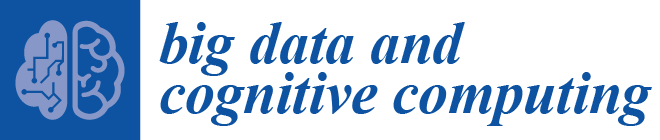

2. Material and Methods

2.1. Mass Segmentation

2.2. Feature Extraction

2.3. Feature Selection

2.4. Bag of Words Modeling

2.5. Image Annotation

3. Results and Discussion

3.5. Decision Making and Discussion